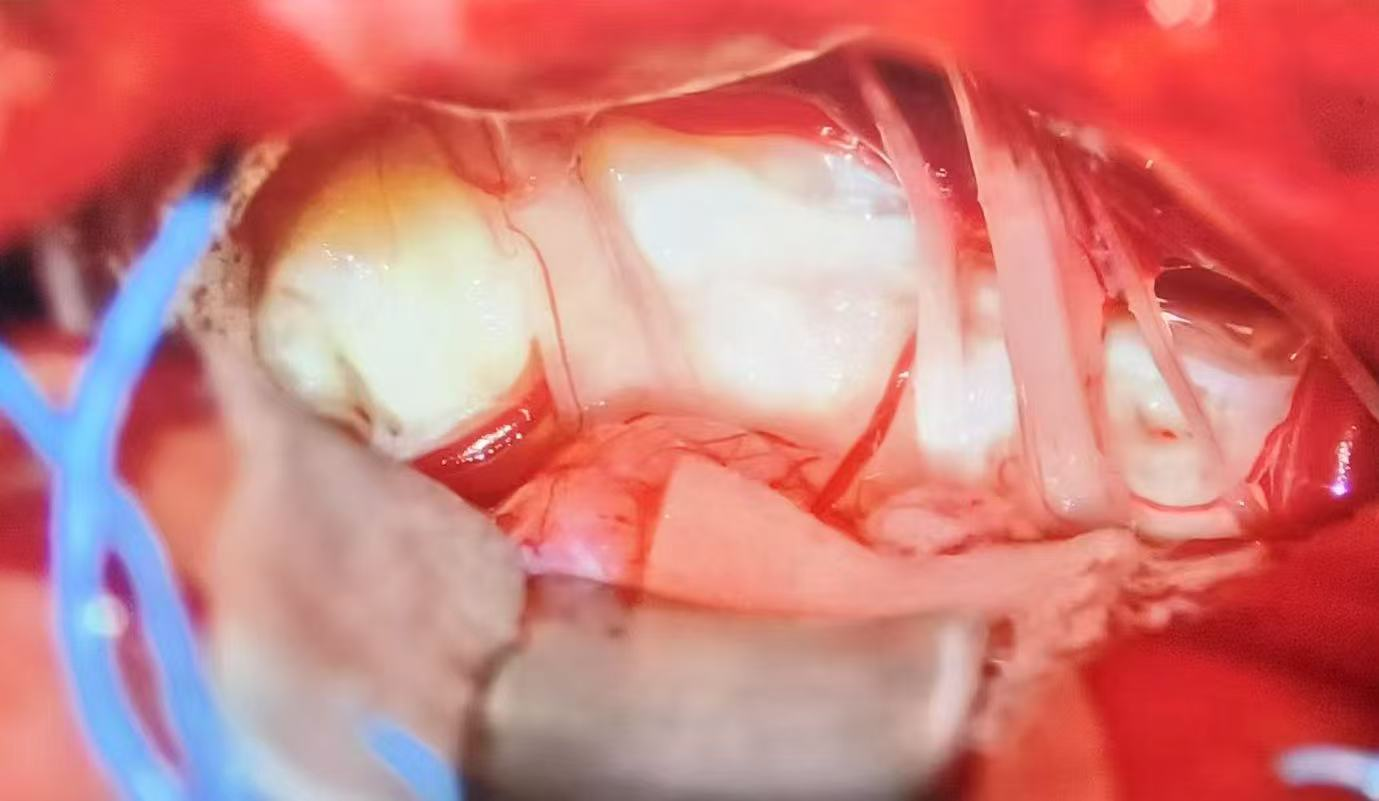

术中

在完善术前准备后,手术如期进行。在麻醉科团队的密切配合下,池超超副主任医师主刀,在显微镜下在毫厘之间精准区分病灶与神经血管,如同在悬崖边跳舞般,将粘连紧密的肿瘤组织一点点剥离、吸除。最终,肿瘤切除满意,且周围的面神经、听神经及脑干功能完好无损。